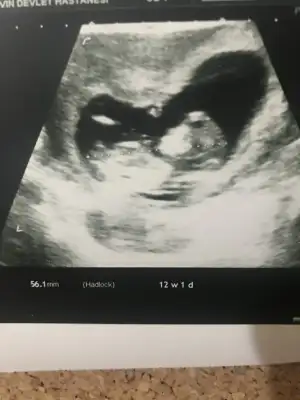

dr soylemeden siz gorun genital nub teorisi ( bebegin cinsiyeti)

• ADAF7E8A-0479-4E58-B45E-697833EDB9DA.webp

ADAF7E8A-0479-4E58-B45E-697833EDB9DA.webp

30,8 KB · Görüntüleme: 31